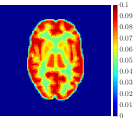

Figure 4, Figure 5, and Figure 6 show the mean images computed over the ten reconstructions obtained by the methods reg-AS-TR, reg-GN, and by the Matlab routine lsqcurvefit implementing a standard Trust-Region-Reflective least-squares algorithm [11, 10]. We used the noise-free IF and the perturbed IF with and of noise, respectively. Figure 7 contains mean and standard deviation values of the kinetic parameters computed over the ten reconstructions and over each one of the four homogeneous regions, for each one of the three noise levels on the IF.

In general, reg-AS-TR and lsqcurvefit seem to provide similar mean reconstructions, although uncertainties associated to lsqcurvefit are significantly bigger. On the other hand reg-GN seems to systematically underestimate the parameter values within region . Furthermore and as expected, for all methods the quality of the parametric reconstructions deteriorates with increasing noise levels; this is more clear from the and parametric images, probably due to the different sensitivities of the data with respect to the model parameters [37]. In reg-GN and lsqcurvefit some artifacts can be observed at the edges of the homogeneous regions, especially around region and region , whereas the effect of regularization in reg-AS-TR results in a reduced presence of artifacts while the structure of the regions is preserved. This general trend is confirmed by the error-bar plots of Figure 7. Finally, the frames in Figure 8 corresponding to reg-AS-TR show a significant improvement of the image quality with respect to what is provided by the other two approaches.